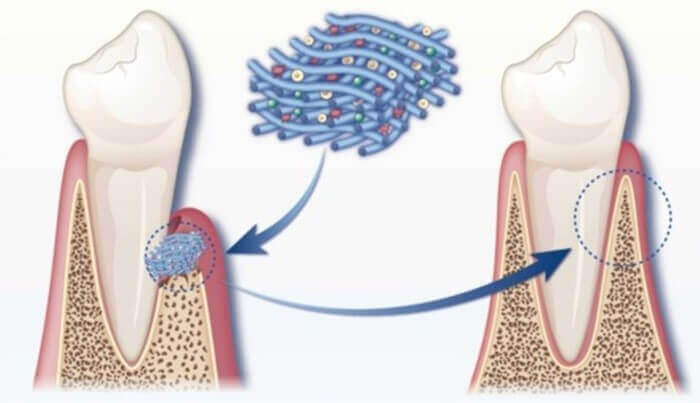

در کنار تغییرات استخوانی، شاهد تغییرات بیولوژیکی حین درمان ارتودنسی در ناحیه بافتهای نرم لثه نیز هستیم که دندانها را با موقعیت جدید هماهنگ میکنند. برخلاف استخوان که پاسخ آهستهتری دارد، لثه (gingiva) بهصورت نسبی سریعتر واکنش نشان میدهد. از حدود هفته دوم به بعد، این بافتها بهتدریج خود را با وضعیت جدید دندانها انطباق میدهند.

با حرکت دندانها، لایههای سطحی لثه دچار کشش یا چینخوردگی میشوند. این تغییرات باعث تحریک فعالیت فیبروبلاستها در بافت همبند زیرین لثه میشود. این سلولها رشتههای کلاژن جدید تولید میکنند تا ساختار لثه را با محل تازهی دندان تثبیت کنند. در ناحیههایی که کشش وجود دارد، حتی ممکن است لثه کمی نازک شود یا به سمت عقب کشیده شود که این مورد نیازمند بررسی بالینی دقیق است.

همچنین در پاسخ به نیروهای مکانیکی، رگزایی (angiogenesis) یا ایجاد رگهای خونی جدید در لثه اتفاق میافتد که به تغذیه بهتر و ترمیم بافت کمک میکند. اگرچه این تغییرات جزئی به چشم نمیآیند، اما نقش مهمی در پایداری طولانیمدت نتایج درمان ارتودنسی دارند و در صورت نادیده گرفتن، ممکن است منجر به مشکلات لثهای یا حتی بازگشت حرکت دندان شوند.